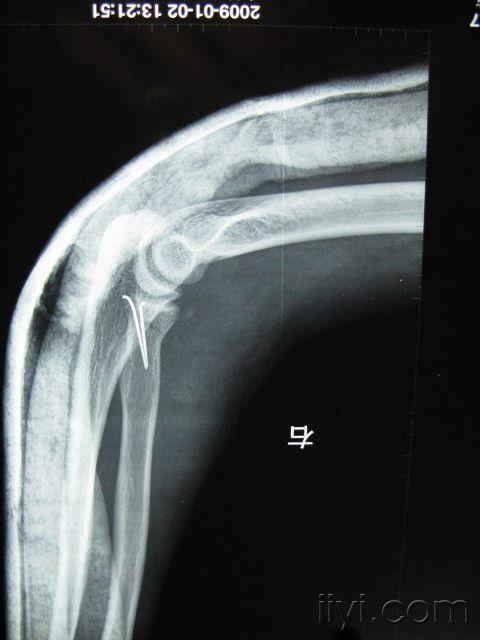

桡骨颈骨折

图片尺寸480x640